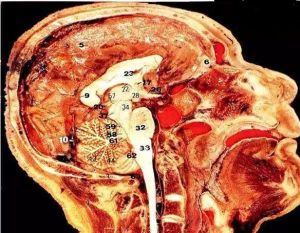

大腦腳屬於中腦水管腹側的部分,呈V字形,前部分開,兩腳之間為腳間窩;內外側分別有中腦內側溝和外側溝,為被蓋與腳底的分界。

大腦腳大腦腳屬於中腦水管腹側的部分。呈V字形,前部分開,兩腳之間為腳間窩;內外側分別有中腦內側溝和外側溝,為被蓋與腳底的分界。內側溝有第3對腦神經與中腦相連。外側溝背側與小腦上腳前外側間三角形區域為丘系三角,內有外側丘系纖維通過。大腦腳分被蓋與腳底兩部。被蓋位於背側,主要成自網狀結構,內含第3、第4對腦神經核、副交感核、紅核、黑質和上下行傳導束等。腳底主要為起自大腦皮質的皮質腦幹束、皮質脊髓束和皮質腦橋束等下行傳導束,是大腦皮層管理隨意運動以及對小腦施加影響的一個主要傳出通路。中樞神經系統